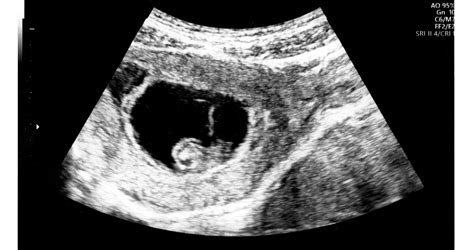

A magzati szívultrahang, más néven magzati echocardiográfia egy kifejezetten a szívfejlődési rendellenességek kiszűrésére alkalmas vizsgálat. A magzati szív vizsgálata a terhesgondozás és a magzat sorsa szempontjából kiemelkedően fontos, és rendkívüli szakértelmet igényel.

Korszerű ultrahang készülék segítségével lehetőség van a szívben áramló vér irányának és sebességének mérésére is, mellyel a szűrés hatékonysága tovább emelhető.